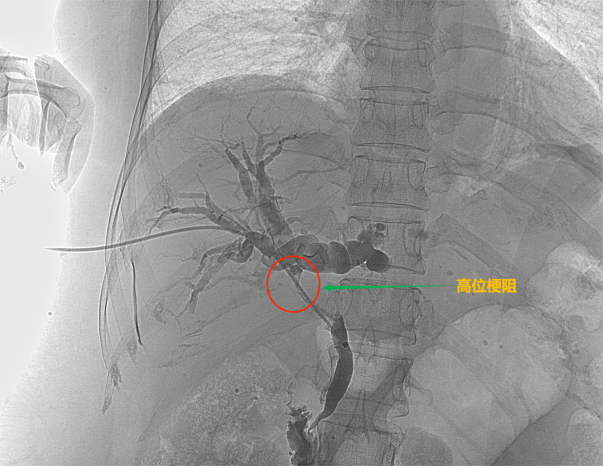

![]() 根据梗阻位置的不同可以分为低位胆道梗阻和高位胆道梗阻 ![]() ![]() ![]() 低位胆道梗阻 ![]() ![]() ![]() 高位胆道梗阻